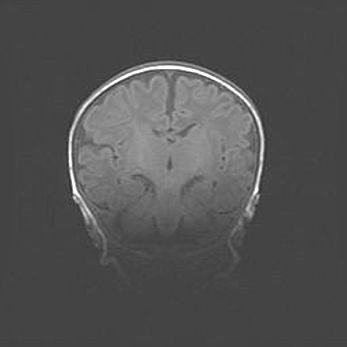

Церебральная ишемия II.

Возраст: 5 дней

Вес: 3400 г

Пол: женский

Окружность головы: 35 см

Срок гестации: 39 недель

Церебральная ишемия – это заболевание, характеризующееся недостаточностью (гипоксией) либо полным прекращением (аноксией) снабжения мозга кислородом по причине закупорки одного или нескольких сосудов. Это приводит к  что метаболическим расстройствам различной степени тяжести в тканях головного мозга, развитию коагуляционных некрозов и гибели нейронов.